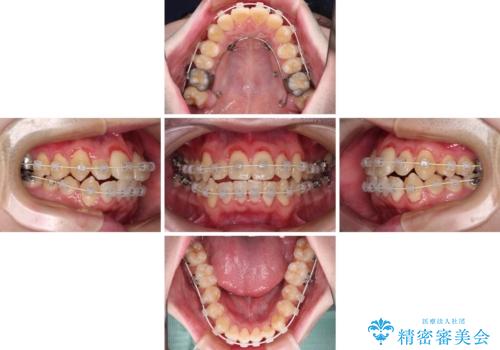

シザーズバイトは強く咬合する奥歯を移動させるため、多くの場合においてワイヤー矯正の装置のみでは改善が困難となります。

奥歯の咬み合わせ改善は治療初期からしっかりとアプローチする必要があるため、補助装置を積極的に利用します。